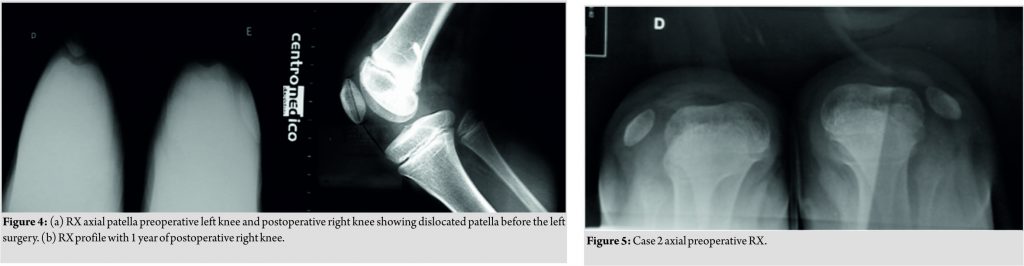

The first patient was 8 years’ old, frequent falls, and bilateral patellofemoral instability. In the preoperative period, the patella of the right knee was dislocated and irreducible (Dugdale V) and the left knee was Dugdale IV. She was submitted to the surgical procedure in the right knee and 1year later in the left one (Fig. 4). We removed the anchors bilaterally in 2011, at the age of 12. No other procedure was necessary, and the functional results and family satisfaction were excellent.

The second child presented with a complaint of recurrent falls, bilateral valgus, bilateral significant femoral anteversion, and the two Dugdale V knees (Fig. 5). At 6 years of age, he was submitted to surgery in the right knee (2010) and in 2011 in the left. As in the right knee he still had subluxation of the patella, we performed in the left knee, an associated and modified Galeazzi procedure reconstructing the medial patellotibial ligament, leaving the semitendinosus inserted in the tibia, and setting the reconstruction with osseous points on the patella medially. After 3years, as valgus of the right knee increased and continued with dislocation in flexion, we performed bilateral medial femoral hemiepiphysiodesis procedure (Fig. 6 and 7).

In 2015, we removed the plaque from the left knee and in 2016 from the right, with the improvement of the patella subluxation and formation of the trochlea (Fig. 8).